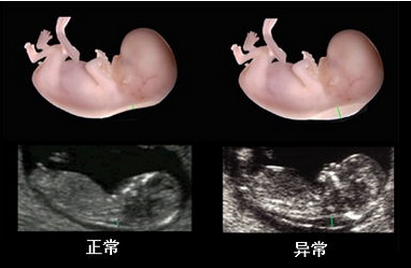

在线咨询随着彩超系统的突飞猛进,系统彩超营运而生,深受孕妈的青睐。系统彩超可以对胎儿进行智力筛查和排畸检查,掌握胎儿生长发育状况,为了能够达到检测的较佳效果,做系统彩超需要注意什么?

贵阳和谐阳光医院引进系统彩超,能够实时获取三维图像,超越了传统超声的限制,能立体、实时地显示人体器官的三维立体结构,为临床超声诊断提供更丰富的影像信息。